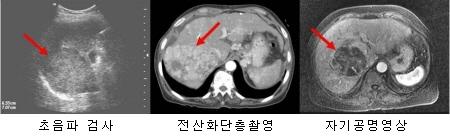

대부분의 암은 진단 시에 조직검사를 실시합니다. 그런데 간암은 좀 달라서, 많은 경우에 조직검사 없이 영상검사와 혈액검사(종양표지자 검사)로 진단하고, 이것만으로 진단이 되지 않는 경우에나 조직검사를 합니다.

예를 들어, 만성 B형이나 C형 간염, 간경변증 등 위험인자가 있는 사람이 복부 초음파검사와 알파태아단백검사(α-胎兒蛋白, AFP; alpha-fetoprotein)에 따라 암으로 의심된다면 역동적 조영증강 전산화단층촬영(dynamic contrast-enhanced CT), 역동적 조영증강 자기공명영상(MRI, magnetic resonance imaging), 간세포특이조영제(gadolinium ethoxybenzyl diethylenetriamine pentaacetic acid; Gd-EOB-DTPA)를 이용한 MRI를 시행하여 암에 합당한 소견을 보일 경우 간암 확진을 하게 됩니다. 한편, 위험인자가 있는 사람에게서 1cm 이상의 결절이 발견되고 위의 영상검사 중 하나 또는 두 가지 이상에서 합당한 소견을 보이면 역시 간암이라는 진단이 가능합니다. 간세포암종 고위험군에 해당하지 않거나, 영상 검사에서 간세포암종의 전형적인 소견을 보이지 않으면, 초음파 영상을 보면서 종괴에 가느다란 바늘을 찔러 넣어 조직을 채취하는 조직검사를 시행하여 진단하게 됩니다.

간암의 진단방법 이미지

[간암의 진단방법]